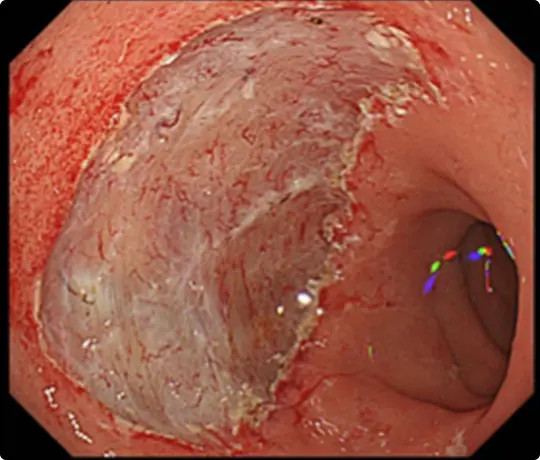

約3cmの大きな大腸ポリープです。

スネアでポリープの根元を縛り、電流を流して切除します(出血予防のためポリープの根元にクリップをうっています)。

切除した検体です。病理検査で早期大腸がんと診断されました。がんは完全に切除されており、治癒と判定されました。